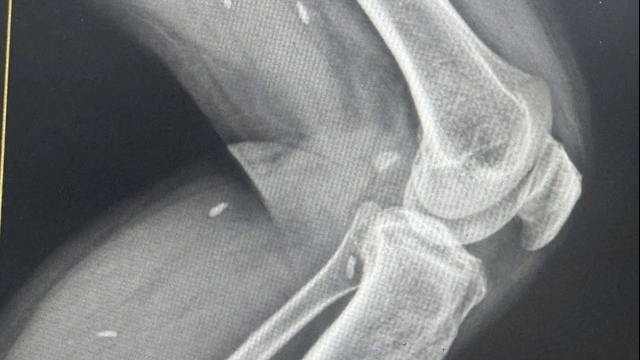

Các bệnh nhi được chỉ định làm xét nghiệm máu, chức năng gan, thận, điện giải đồ, siêu âm, X - Quang… và được bù nước, điện giải. Đến 1h30 ngày 22/1, BVĐK tỉnh Tuyên Quang chuyển 5 bệnh nhân về BV Nhi Trung ương để theo dõi, xử trí kịp thời diễn biến bất thường có thể xảy ra.